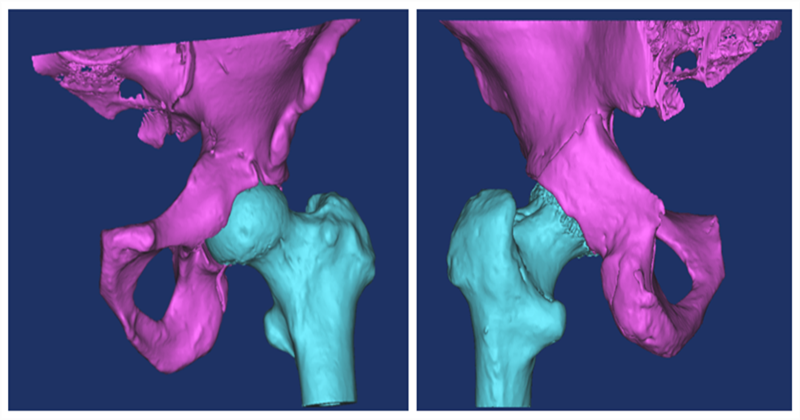

术前在刘利主任带领全科医生针对该病例进行了术前讨论,制定手术计划。张洪彬主管医师利用MIMICS影像软件对患者的CT数据进行了提取,并进行重新建模,在得到三维图像后,切割、分离得到单独的髋臼影像。大家通过360°全方位对该病例三维影像进行研讨、观摩,初步制定手术计划为K-L入路行后壁骨折复位,钢板螺钉固定,前柱通道螺钉固定横行骨折。但是难点在于在没有手术导航的条件下如何精准打入髋臼前柱通道螺钉。

我们应用软件自动建立虚拟骨盆三维仿真模型,应用相关软件功能模块建立虚拟圆柱体替代拉力螺钉,将虚拟圆柱体置入髋臼前柱骨质内,逐渐增大虚拟圆柱体的直径直至髋臼前柱骨质边缘,在三维层面中记录虚拟圆柱体的直径及长度,并测量入钉点与相关髋臼解剖结构的距离,测量虚拟圆柱体的入钉角度及螺钉在骨盆正位、入口位与骨盆正中线的夹角。在得到精准的螺钉入点、长度、角度等测量值后,为术中置钉提供了较为重要的参考价值。

(进行图像分割后获得骨盆髋臼,模拟髂骨斜位与骨盆入口位)